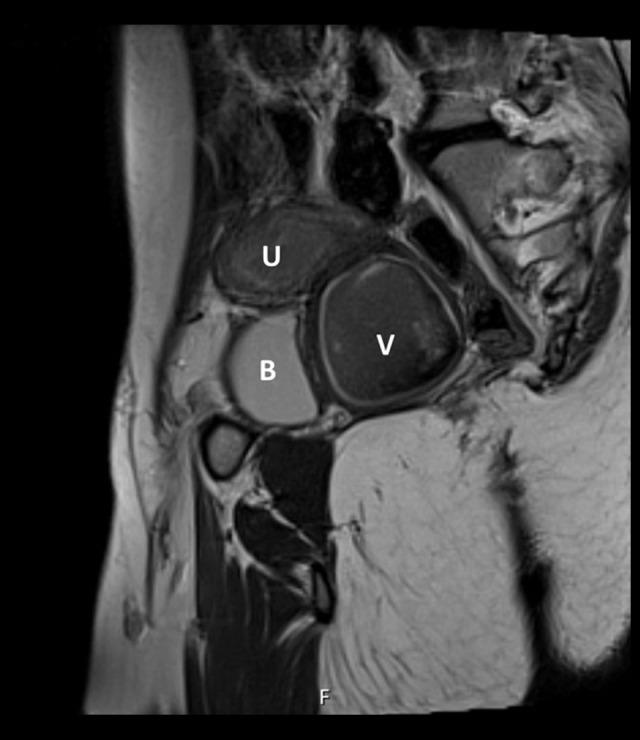

BACKGROUND Caudal regression syndrome (CRS) is a rare anomaly characterized by maldevelopment of the caudal half of the body and can involve the genitourinary system. This report presents the case of a 13-year-old girl diagnosed with CRS and previously unknown distal vaginal atresia, presenting with monthly pelvic pain. CASE REPORT A 13-year-old pre-menarcheal patient with CRS sought emergency care due to debilitating monthly pelvic pain persisting for 3 months. Pelvic examination revealed the absence of a vaginal opening, and a rectal exam showed a 5-cm large bulge anteriorly, along with a 2-cm fibrous septum in the distal portion of the vagina. Pelvic ultrasound and magnetic resonance imaging confirmed the presence of hematometrocolpus and hematosalpinx on the right adnexa, while the left ovary was not identified. Treatment commenced with fixed analgesia and combined continuous oral contraception. Due to the persistent pain and uncertainty regarding the anatomy of the internal reproductive organs, diagnostic laparoscopy with drainage of the hematocolpus was performed 2 weeks later. Six months later, after multidisciplinary discussion, definitive surgery (pull-through vaginoplasty) was carried out, allowing for emotional preparation for postoperative dilation. One year after the definitive surgery, the patient remains asymptomatic, experiencing regular withdrawal bleeding with no signs of obstruction. CONCLUSIONS Patients with musculoskeletal anomalies should undergo urogenital tract evaluation. Timely identification of distal vaginal atresia is pivotal for devising appropriate treatment and averting complications. During the acute phase, laparoscopic drainage can alleviate symptoms and clarify anatomy, without compromising the success of subsequent definitive surgery.